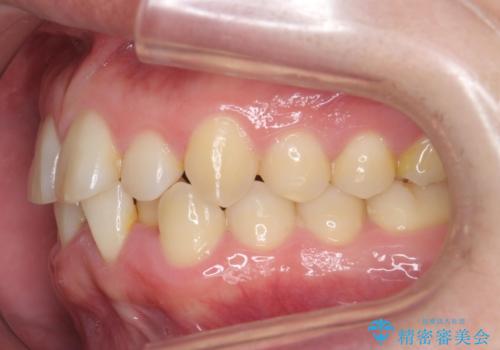

前歯のすき間 歯のがたつき

- 前歯のすき間とがたつきを主訴に来院。

右上の前歯は過去にがたつきがあったとのことで抜いてしまっていました。

歯の数を合わせるために、下の歯を1本抜いて矯正しています。

下の前歯を抜歯したことでブラックトライアングルができましたが、仕上げにIPRを加えることで目立たなくすることができました。